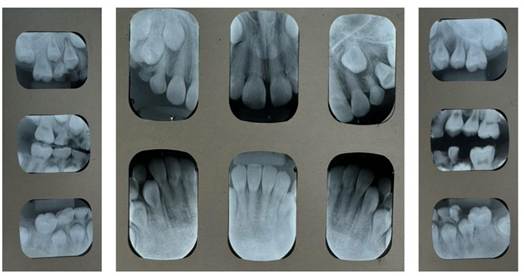

Figura 10. Radiografías periapicales

Se observa a mayor detalle la obliteración de los conductos radiculares en las piezas permanentes, hallazgo radiográfico común en pacientes con amelogénesis imperfecta.